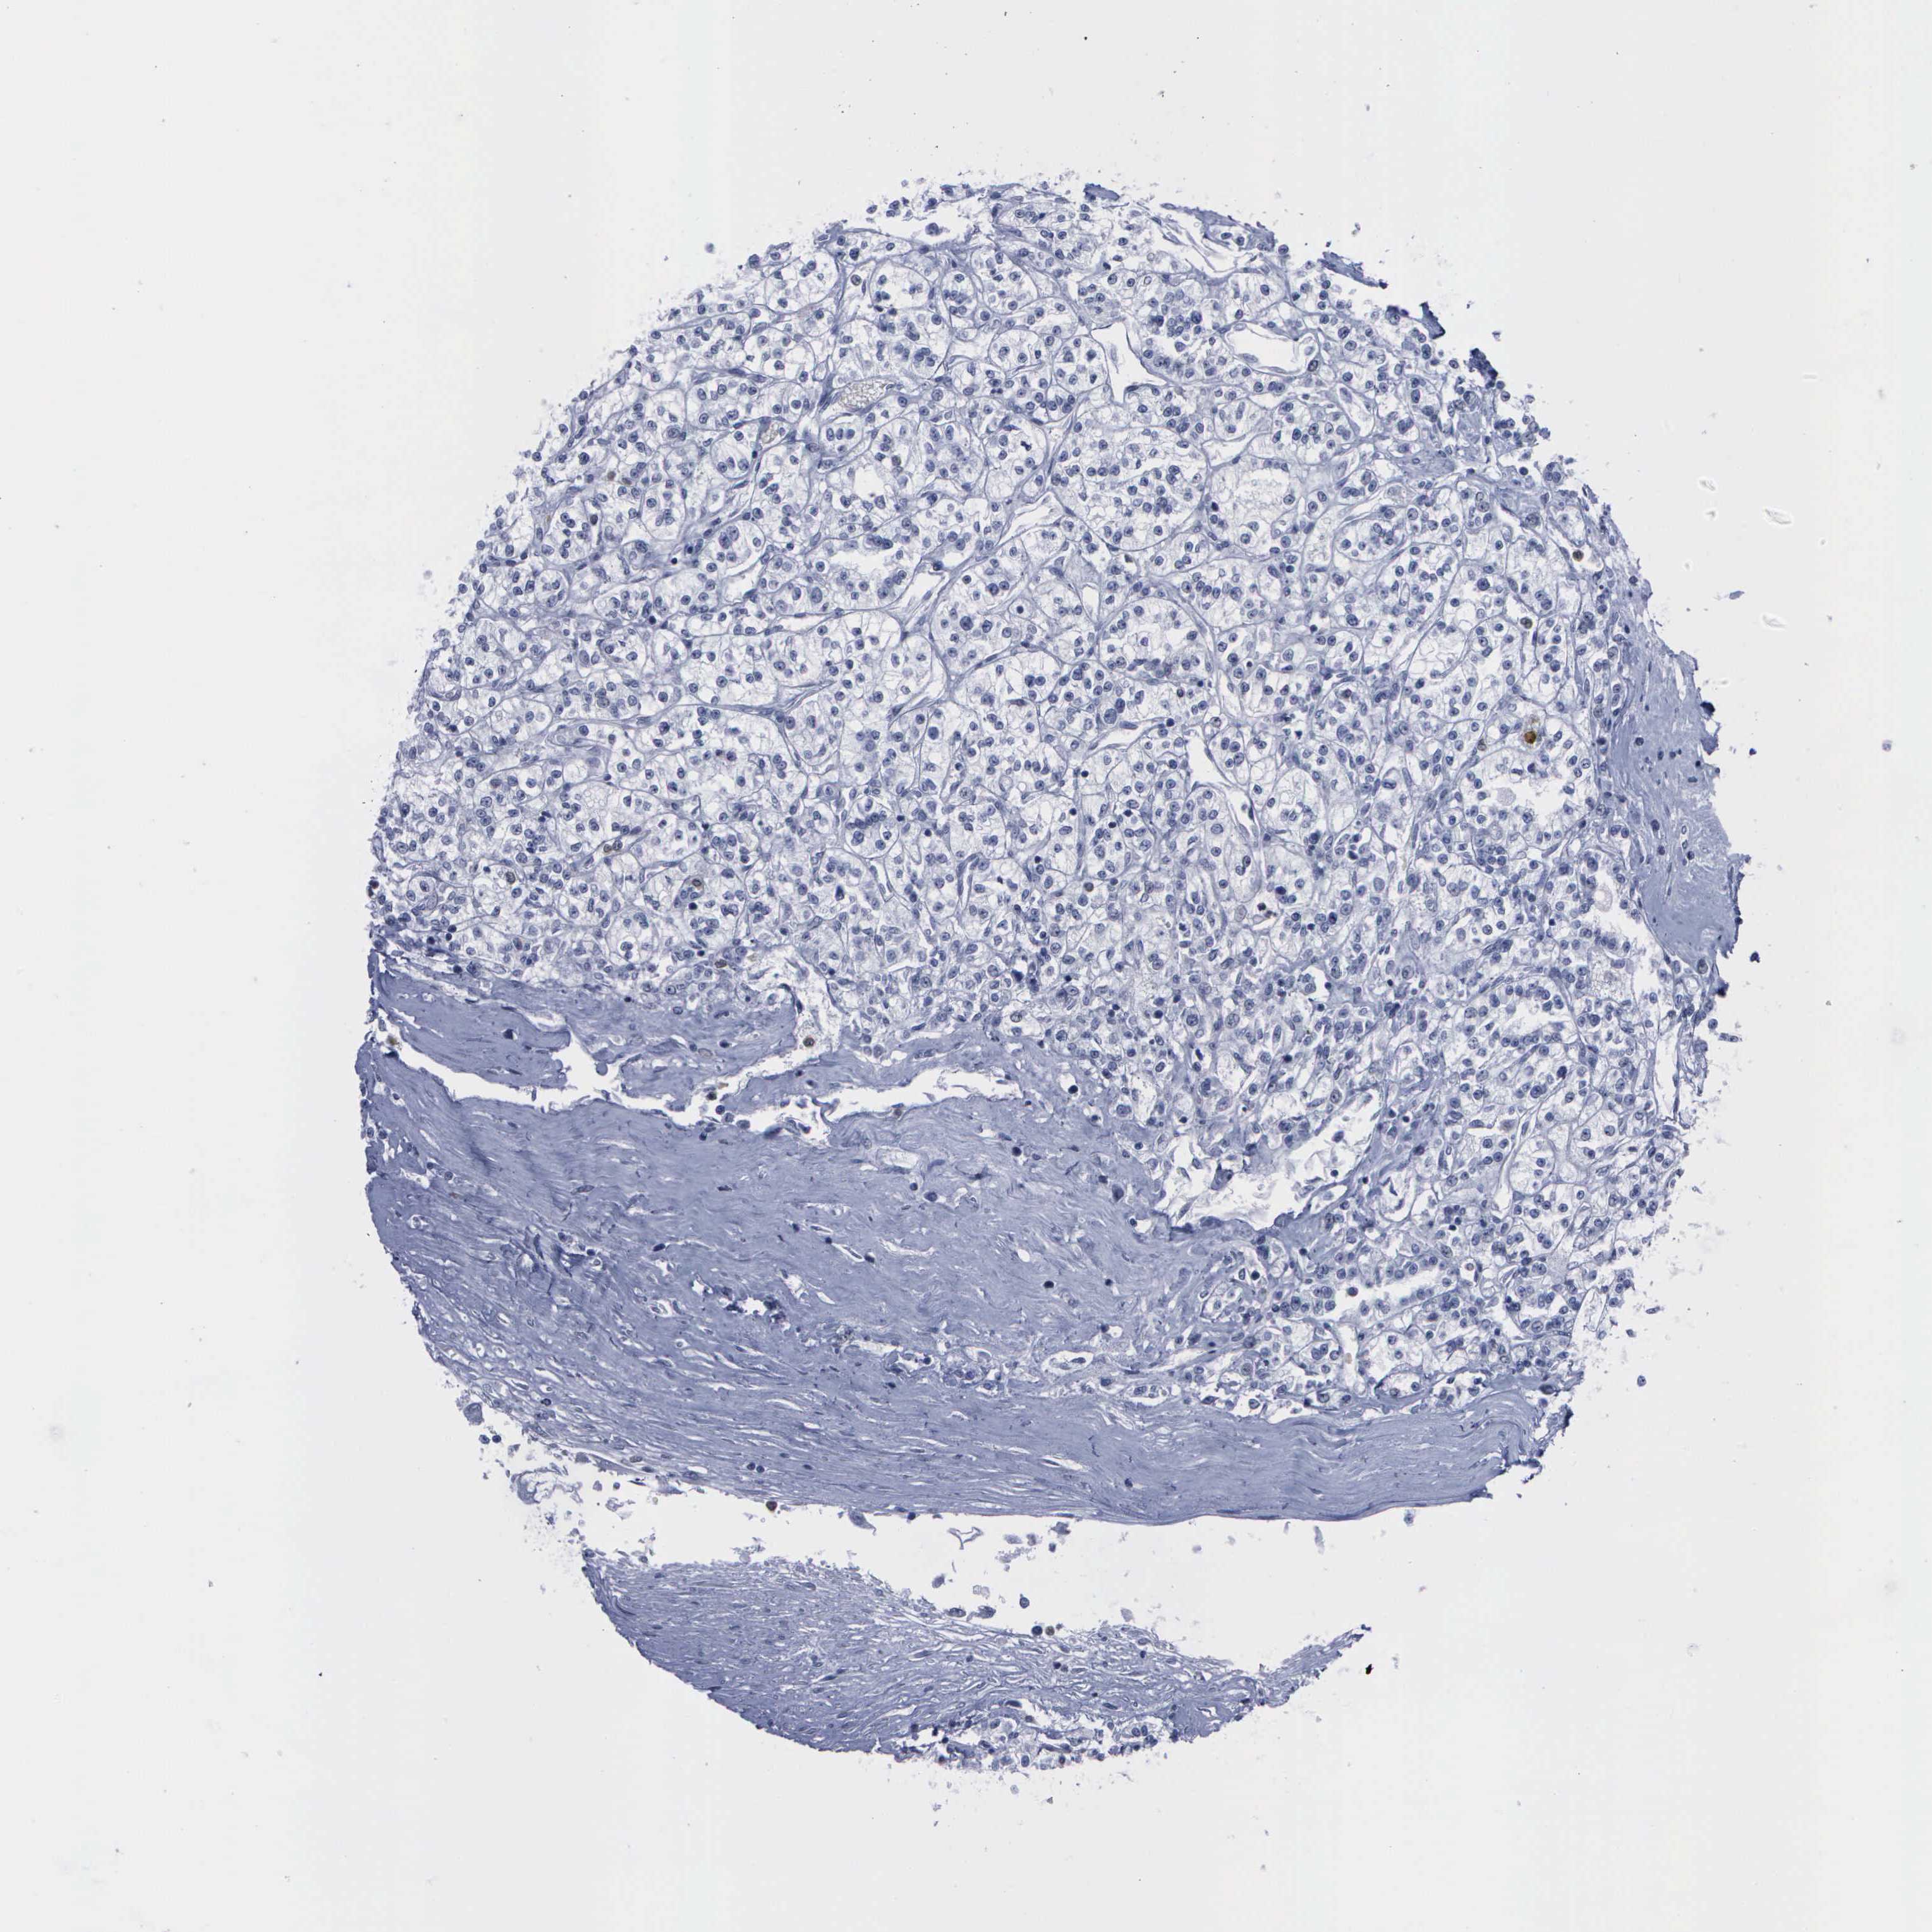

KIDNEY RENAL CLEAR CELL CARCINOMA (VALIDATION) - Interactive survival scatter ploti

The Survival Scatter plot shows the clinical status (i.e. dead or alive) for all individuals in the patient cohort, based on the same data that underlies the corresponding Kaplan-Meier plots. Patients that are alive at last time for follow-up are shown in blue and patients who have died during the study are shown in red.

The x-axis shows the expression levels (FPKM) of the investigated gene in the tumor tissue at the time of diagnosis. The y-axis shows the follow-up time after diagnosis (years). Both axes are complimented with kernel density curves demonstrating the data density over the axes. The top density plot shows the expression levels (FPKM) distribution among dead (red) and alive patients (blue). The right density plot shows the data density of the survived years of dead patients with high and low expression levels respectively, stratified using the cutoff indicated by the vertical dashed line through the Survival Scatter plot. This cutoff is automatically defined based on the FPKM cutoff that minimizes the p-score. The cutoff can be changed by dragging the vertical line or by entering a cutoff value in the square labeled "Current cut-off".

Under the Survival Scatter plot the p-score landscape (black curve; left axis) is shown together with dead median separation (red curve; right axis). Dead median separation is the difference in median mRNA expression between patients who have died with high and low expression, respectively. It is calculated as follows: median FPKM expression of dead patients with high expression - median FPKM expression of dead patients with low expression. This is intended to aid the user in visually exploring custom cutoffs and the associated p-scores and dead median separation.

Individual patient data is displayed and can be filtered by clicking on one or more of the category buttons on the top of the page. Categories describing expression level and patient information include: high, low, alive, dead, female, male and tumor stages. The scale of the x-axis can be toggled between linear and log-scale by clicking on the "x log" button. Mouse-over function shows TCGA ID, patient information and mRNA expression (FPKM) for each patient.

& Survival analysisi

Kaplan-Meier plots summarize results from analysis of correlation between mRNA expression level and patient survival. Patients were divided based on level of expression into one of the two groups "low" (under cut off) or "high" (over cut off). X-axis shows time for survival (years) and y-axis shows the probability of survival, where 1.0 corresponds to 100 percent.

CSTA is not prognostic in Kidney Renal Clear Cell Carcinoma (validation)

Best expression cut offi

Based on the FPKM value of each gene, patients were classified into two groups and association between prognosis (survival) and gene expression (FPKM) was examined. The best expression cut-off refers the FPKM value that yields maximal difference with regard to survival between the two groups at the lowest log-rank P-value. Best expression cut-off was selected based on survival analysis .

When clicking on this number, the vertical dashed line indicating cut-off, the interactive survival plot, and the Kaplan-Meier curve will be adjusted to show results based on the best expression cut-off.

: 19.04

Median expressioni

Median expression refers to the median FPKM value calculated based on the gene expression (FPKM) data from all patients in this dataset. When clicking on this number, the vertical dashed line indicating cut-off, the interactive survival plot, and the Kaplan-Meier curve will be adjusted to show results based on the median expression.

: N/A

Median follow up timei

Median follow up time refers to the median time (years) after diagnosis with this type of cancer, based on clinical data from all patients in this dataset.

P scorei

Log-rank P value for Kaplan-Meier plot showing results from analysis of correlation between mRNA expression level and patient survival.

N/A

5-year survival highi

5-year survival for patients with higher expression than the expression cutoff.

For melanoma and glioma, 3-year survival is shown.

5-year survival lowi

5-year survival for patients with lower expression than the expression cutoff.

Average pTPM 15.1

Number of samples 100